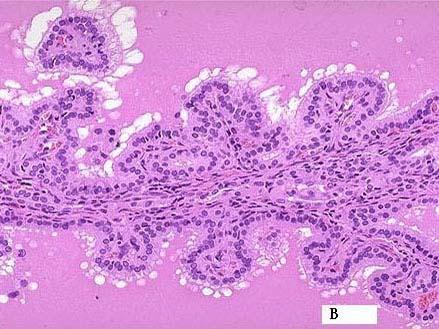

问题 女性甲亢患者,24岁,服用药物治疗2年,近因心悸,多食,消瘦,月经量少就诊,查体甲状腺Ⅱ肿大立即行甲状腺切除术,术后病理巨检示:灰红结节状组织12cm×10cm×5cm,切面灰红色,被膜完整。镜检如下图,根据相关资料可诊断为 ( )

选项 A.结节性甲状腺肿 B.单纯性甲状腺肿 C.胶样甲状腺肿 D.毒性甲状腺肿 E.桥本氏病

答案 B